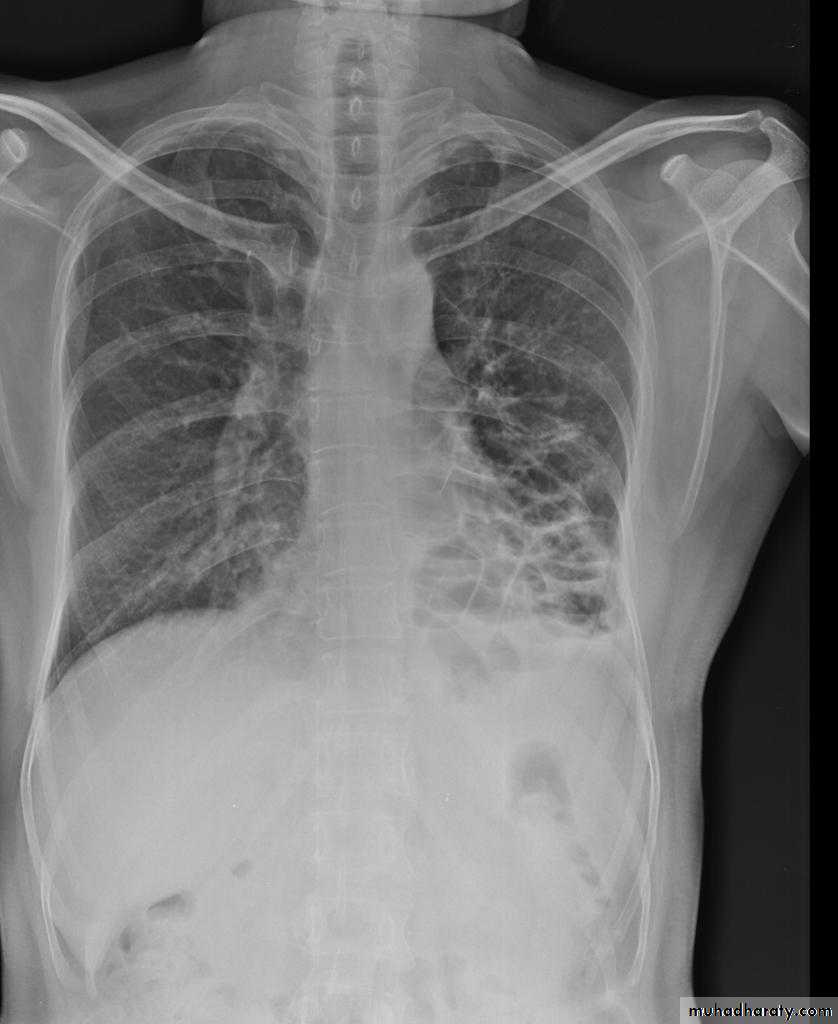

Post primary TB radiographic appearance

Post-primary pulmonary tuberculosis, also known as reactivation tuberculosis or secondary tuberculosis occurs years later, frequently in the setting of a decreased immune status. In the majority of cases, post-primary TB within the lungs develops in either :

* posterior segments of the upper lobes

*superior segments of the lower lobes

Typical appearance of post-primary TB

1.patchy consolidation or poorly defined linear and nodular opacities in both apices , upper zone in one lung , & lower zone in other lung ( ulternating lesion ) .2. Post-primary infections are far more likely to cavitate with multiple abscess formation & air fluid level more develop in the posterior segments of the upper lobes.